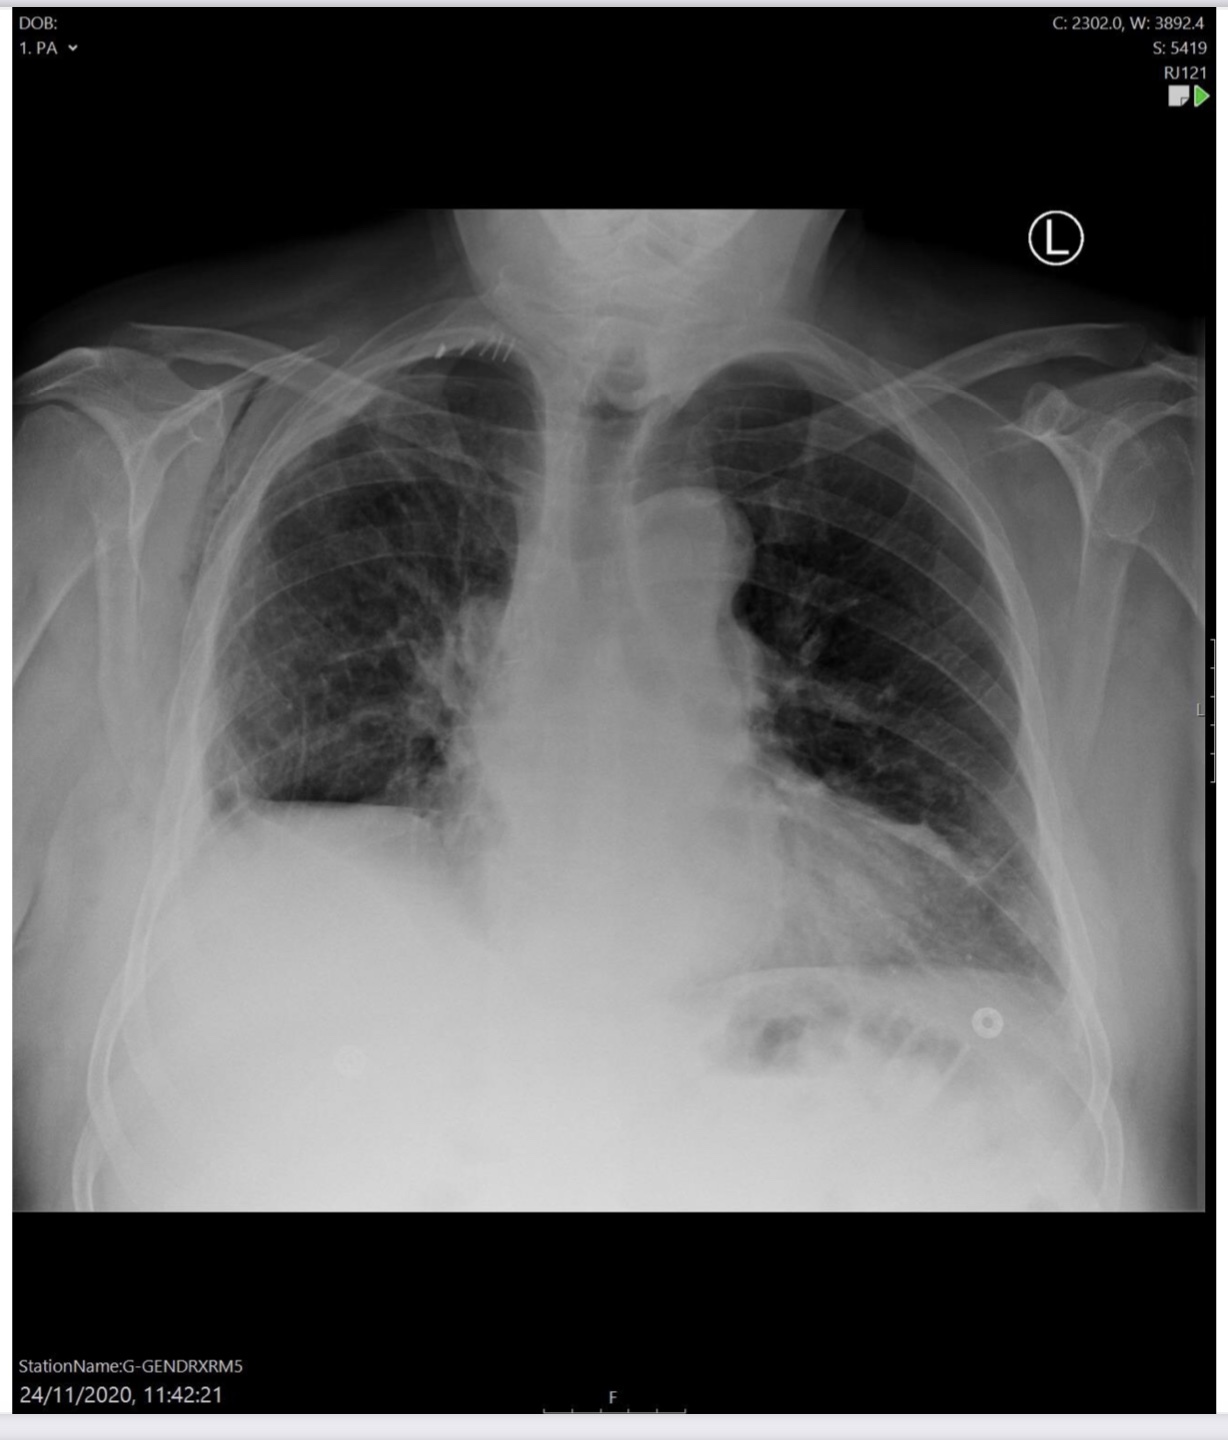

Right lower lobectomy